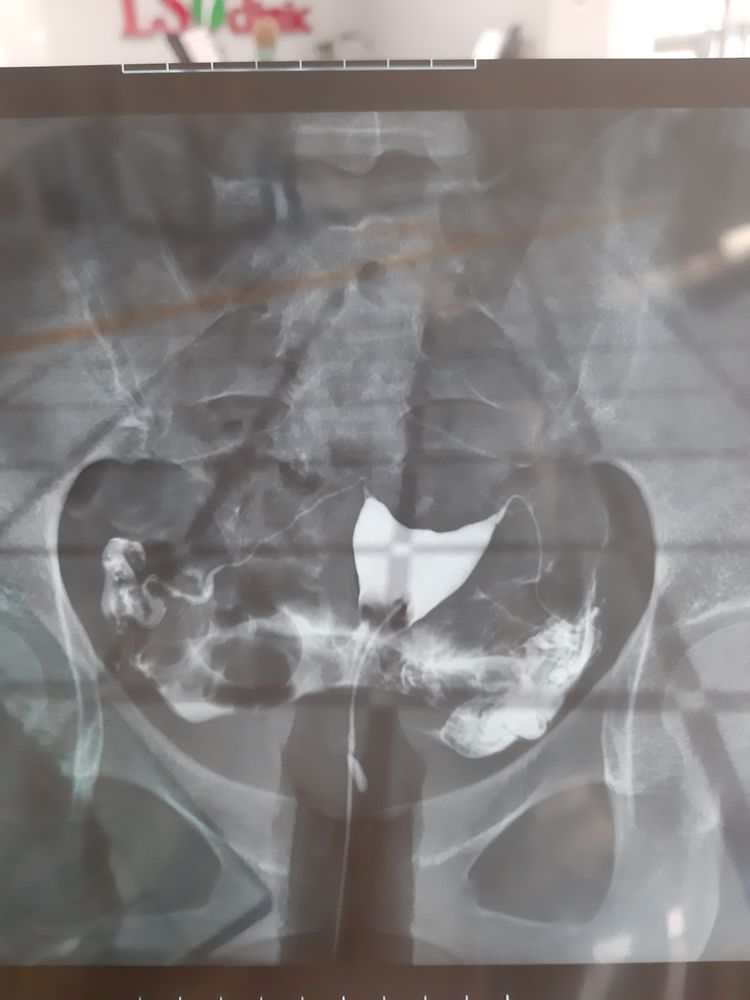

МСГ. С правой трубы контрастное вещ-во с трудом прошло

Стоит ли пить КОК и делать МСГ? Беременность в цикле МСГ